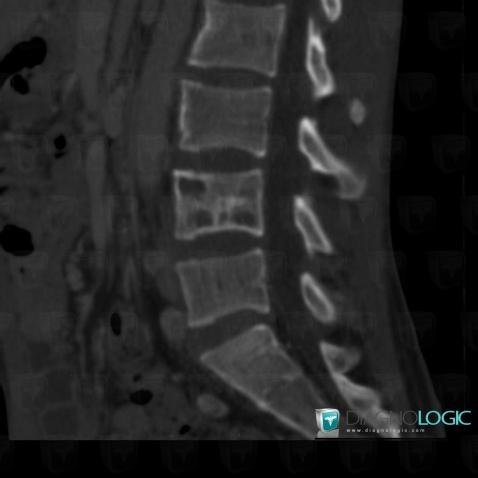

Tuberculosis, Mediastinum, Theoretical

Here is the specific information in the key image above:

- Diagnosis Tuberculosis (link to Osteomyelitis), Location(s) Mediastinum, with gamuts Paraspinal line shift